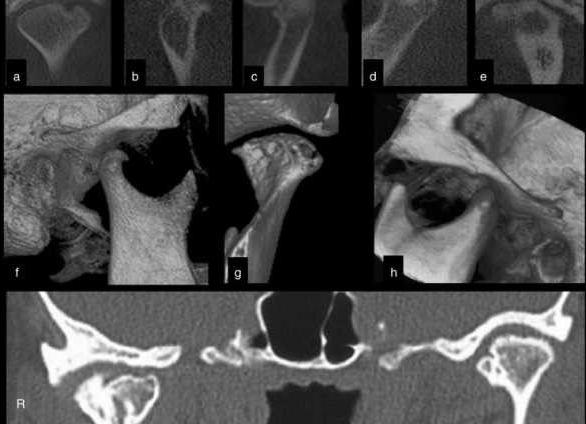

Кт забрюшинного пространства

КТ забрюшинного пространства — это метод исследования тканей с использованием рентгеновских лучей, при котором доктор получает послойное изображение нужных органов в заданной плоскости. Высокая точность и информативность этого метода исследования позволяет с большой вероятностью поставить верный диагноз и составить правильную схему лечения.